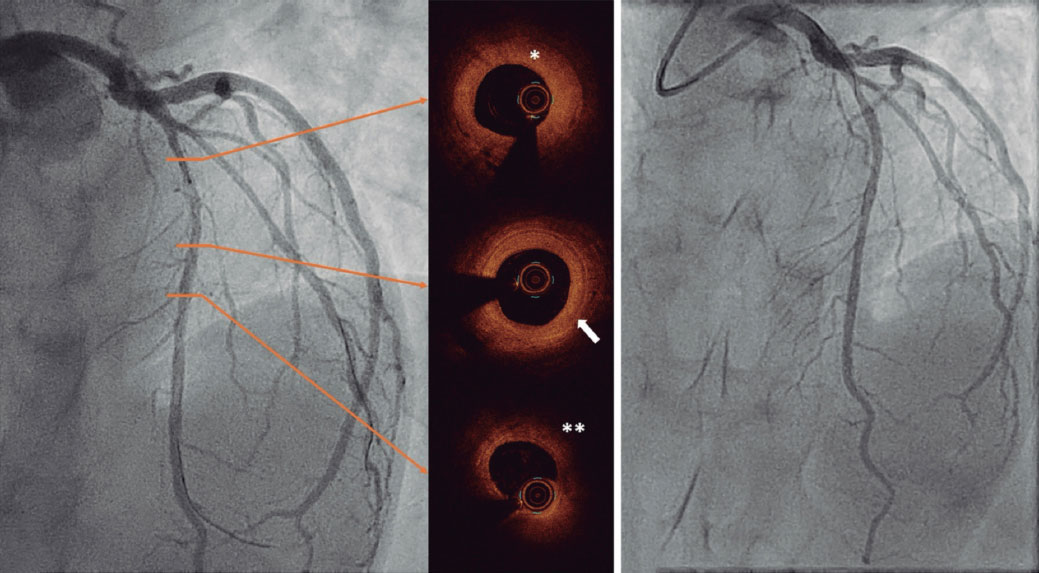

In 2024, repeat coronary angiography for exertional angina showed RCA disease progression with larger mid-RCA calcification, confirmed by OCT of the same artery segment. Furthermore, the distal segment showed disease progression with intima thickening and medial disruption (figure 1; figure 1E-1H). A new critical stenosis was found in the left anterior descending coronary artery. Furthermore, a biopsy was obtained from an aneurysmal segment of the temporal artery (figure 2). Histopathological findings were similar to those seen on the OCT of coronary arteries. The thickened arterial wall was characterized by fibrous/myofibroblastic intimal hyperplasia, acute inflammatory infiltrate, necrosis, and fibrinoid changes (figure 2A-arrow). Moreover, a loss of the internal elastic lamina (figure 2B-arrow and figure 2A- asterisk) and adventitial vessels confirmed the presence of perivascular chronic inflammation.

Figure 2.